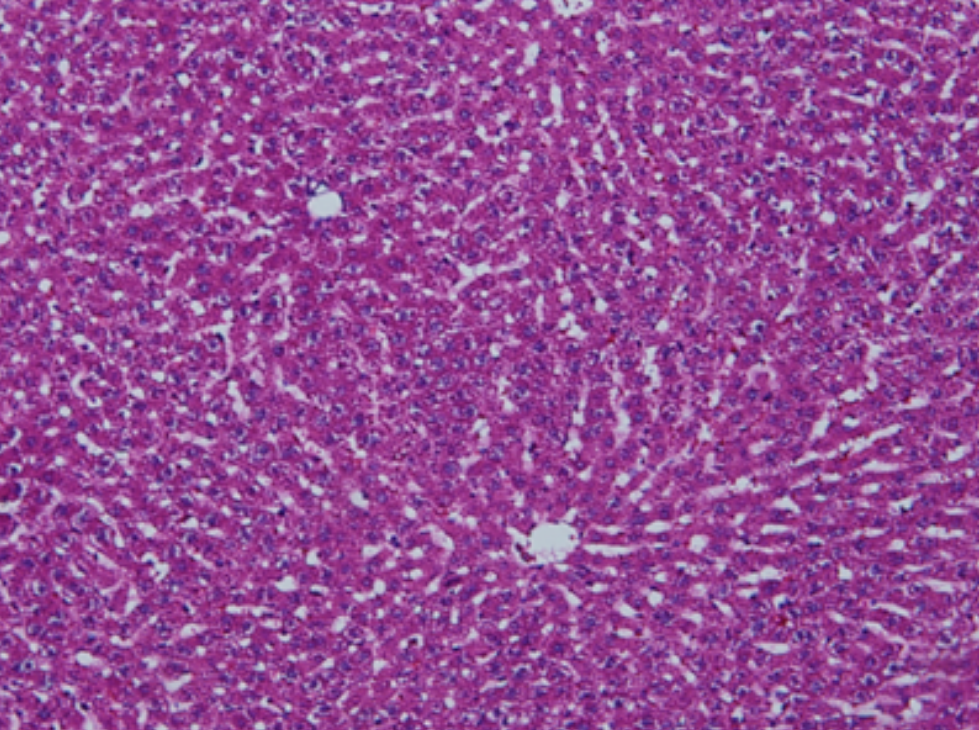

形成原因:切片经梯度乙醇处理后没有完全脱水,导致二甲苯透明、中性树胶封固后残留大量水分。 解决方法:首先移去盖玻片,用二甲苯溶解封固剂如中性树胶,再将切片置入无水乙醇内,待切片重新脱水完全后,用二甲苯透明处理,中性树胶封固。要注意所有用于脱水和透明的液体,在使用一定时间后,应及时更换。 二、细胞核呈红、棕色 形成原因:苏木精染色液过度氧化,切片在苏木精染液染色后返蓝不足。 解决方法:每次染色之前检查苏木精染色液的染色能力,发现苏木精染色液氧化过度应及时更换。此外,切片经苏木精染色后,要给切片以足够的蓝化时间,蓝化过程可用流水、温水、弱碱性溶液(如稀氨水或0.2%碳酸氢钠)等处理。 三、切片在脱蜡后出现大片白色斑点 形成原因:由于烤(烘)片温度太低,切片上的组织蜡膜在脱蜡前没有充分烤(烘)融化。或是因为切片在二甲苯液中停留时间不足,或二甲苯使用过久,造成的脱蜡不彻底。 解决方法:若是由于切片烤(烘)温度低所致,可以先用二甲苯去除切片上的封固胶,然后重新用二甲苯脱去切片上的石蜡,再进行后续染色。若是由于切片在脱蜡的二甲苯中停留时间不足或脱蜡二甲苯使用过久浓度不足所致,则需将切片退回到二甲苯中,停留较长时间,或更换二甲苯液体重新脱蜡,再入乙醇重新脱二甲苯,入0.5%盐酸水溶液褪色后,重新HE染色。 四、细胞核苍白暗淡,即苏木精染色太淡 形成原因:切片在苏木精染色液停留时间太短;苏木精染色液过度氧化,失去染色能力,不能再继续使用;分化步骤处理时间过长;固定不及时。此外值得注意的是,若骨组织细胞核暗淡,大多是脱钙过度造成的。 解决方法:切片重新染色。如果组织在酸性固定液(如Zenker、Bouin)或非中性缓冲甲醛液固定时间过长,细胞核染色能力将减弱,需增加其在苏木精染色液的时间,或用一些方法增加组织的嗜碱性,以改善细胞核的着色。例如,上述组织玻片可以使用Weigert铁苏木精染色液。如果组织是用Zenker液固定的,可将切片脱蜡后放在5%碳酸氢钠溶液3~4h,流水冲洗5min后染色。如果组织是用Bouin液固定的,可将切片脱蜡后放在5%碳酸锂1h,流水冲洗10min后染色。 五、细胞核过染,苏木精染液占据了细胞质 形成原因:玻片在苏木精染色液停留时间过长,或是切片太厚、分化步骤时间太短。 解决方法:如果不是因为切片太厚(用显微镜仔细上下微调,只有一二层细胞核层次),就需将切片进行脱色、漂白、重新染色,适当调整染色和分化时间。但如果确定是由于切片太厚导致的细胞核过染,则需要重新切片。 六、伊红着色淡 形成原因:可能是伊红染液pH值大于5,也可能是蓝化液残留过多,切片太薄,或是切片经伊红染色后在乙醇脱水时间过长。 解决方法:检查伊红染液pH值,必要的话,用乙酸将其调节在4.6~5.0之间,从而使伊红染色色彩艳丽。此外,确保每次蓝化步骤完成后,使用的弱碱性溶液被充分洗去,玻片上没有残留的弱碱性溶液。最后,检查切片的厚度,且脱水时不要让切片在低浓度乙醇中停留时间过长,因为含水多的低浓度乙醇会将切片伊红的颜色分化掉。 七、细胞质过染、分色不足 形成原因:伊红染色液浓度太高,特别是存在焰红燃料、四溴四氯荧光素钠。切片在伊红染色时间过长,或是切片在伊红染色后经乙醇脱水步骤时时间太短,而使乙醇分化伊红的作用不能产生,都能够使细胞质过染。 解决方法:适当稀释伊红染色液,减少伊红染色时间,或使切片在乙醇脱水等步骤时,停留时间相对均匀。同样,也要检查切片的厚度是否合适。 八、切片中出现蓝黑色沉淀物 形成原因:苏木精染色液中的金属膜黏附在玻片上。 解决方法:染色前仔细过滤苏木精染色液,建议使用半氧化苏木精染色液,如Gill苏木精染色液,可以避免过多的金属膜产生。 九、光镜下切片某些区域难以聚焦 形成原因:盖玻片上可能有封固切片的封固剂。 解决方法:移去盖玻片,重新用干净的盖玻片封片。检查切片封片方法,是人工手工封法,还是机器自动封法,如有问题及时调整。 十、封固剂从盖玻片与载玻片之间的缝隙回缩 形成原因:盖玻片弯曲或不平整,或是封固剂含二甲苯过多,稀释过度。 解决方法:移去盖玻片,重新找一张盖玻片,用干净的封固剂封片。如用手工封片法,保证在封固结束时,封固剂容器盖子为紧闭状态。且尽量使用小的容器盛装封固剂,一旦封固剂太黏稠,就可以选择废弃。 十一、细胞核呈灰蓝状态 形成原因:可能由于组织处理温度过高、过热,在液体石蜡中停留的时间过长。或是固定时间太短后,直接在高浓度的乙醇中进行了脱水处理。 解决方法:理论上来说,仅在组织浸蜡步骤才进行加热,组织不能在热蜡液中停留太久。如果由于某些原因不能进行下一步包埋处理,可将组织连同塑料包埋盒一并放置在室温空气中,冷却凝固,以备包埋。待需要包埋时再重新加温直至石蜡融化即可。组织在处理前必须确保固定良好,脱水最好能从低浓度的乙醇开始。 十二、类色素的点状结晶和黑色光滑细胞核 形成原因:这种裸核改变是因为切片封片前放置在空气中的时间太长,以至于二甲苯挥发,切片干燥。 解决方法:移去组织切片上的盖玻片和封固剂,重新处理。将切片水洗数分钟,然后重新脱水、透明、封固。封片过程中要保持组织切片的轻度湿润,尽量不要让其干燥。 十三、染色过淡或过浓 解决方法:如果染色过淡,可以增加染色剂的浓度、延长染色时间或更换新鲜的染色剂;如果染色过浓,则应减少染色剂的浓度或缩短染色时间。 十四、切片出现叠加褶皱 形成原因:新购买的玻片洁净度不够、用镊子撑开切片时操作不够熟练未能平整伸展,或玻片表面有油脂,切片粘贴不牢。另外,烤片时间不足、烤片温度过低或切片过厚造成切片脱落,都会造成重叠或有皱褶的情况。 解决方法:新购买的玻片最好能用硫酸清洁液浸泡一晚,然后流水冲洗干净。在适宜的温度下烤片时间宁长勿短,保证有充足的烤片时间和温度。另外,切片刀要锋利,才能切出厚薄适宜的切片,保证切片不会因为过厚而脱落。 十五、组织残缺不全或有刮划痕迹 形成原因:组织残缺不全是由于切片时修整蜡块时深度不够、组织没有全部暴露于切面。切片的刮划痕迹是由于切片刀的刀锋有缺口、包埋的组织有异物,或是钙化组织、骨组织及包埋石蜡有沙粒造成的。 解决方法:修整蜡块时保证组织块全部暴露于切面,切片时保证切片刀的锋利没刀口。同时在组织取材时去除手术异物和钙化组织。最后,骨组织要完全脱钙,这样可以保证切片的完整和平整美观。 *注:由于实验中导致结果出现误差的原因多种多样,以上内容仅供参考,具体根据实际情况进行判断。